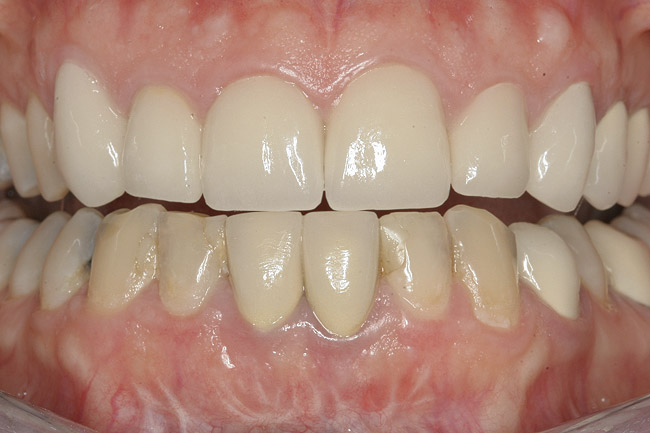

After the zirconia abutments were torqued to 20 Ncm, cotton and composite were used to cover the screw access openings. Figure 7 and Figure 8 show the finished feldspathic porcelain crowns on implants in sites Nos. 24 through 26, and on teeth Nos. 22, 23, 27, and 28; all crowns were cemented with dual-cure resin cement. Good remodeling of gingival architecture is also apparent in Figure 7. As predicted, the free gingival margin (FGM) on No. 23 is approximately 2 mm coronal to those of the adjacent implant crowns on Nos. 24 through 26 (Figure 7); as per the patient’s initial statement, this discrepancy was not an esthetic concern to her. Figure 9 shows the final post-restoration periapical view.

This patient faced a unique situation, perhaps not previously reported: retaining a healthy mandibular lateral incisor knowing this would create an esthetic compromise. Indeed, while the discrepancy in gingival-margin height is noticeable in retracted view (Figure 7), it does not show in full smile (Figure 8).

Figure 7  Finished feldspathic crowns, teeth Nos. 22, 23, 27, 28, and implant sites 24 through 26 showing good gingival emergence profile—post-cementation facial view.

Figure 7

Figure 8  Full smile—finished feldspathic crowns on teeth Nos. 22, 23, 27, and 28; implant crowns in sites 24 through 26; esthetic harmonization with opposing dentition.

Figure 8